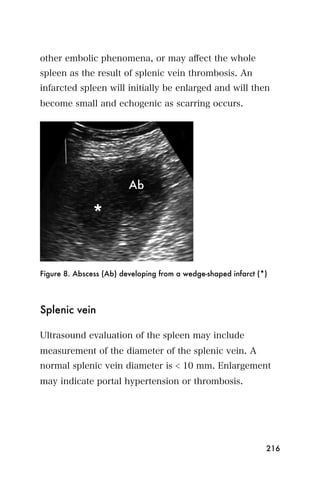

probe s position and angle and be sure the depth setting

is adequate. As a landmark, you may see the bony

cortex of the distal femur (or less likely proximal tibia) in

the far field just beyond the popliteal vessels.